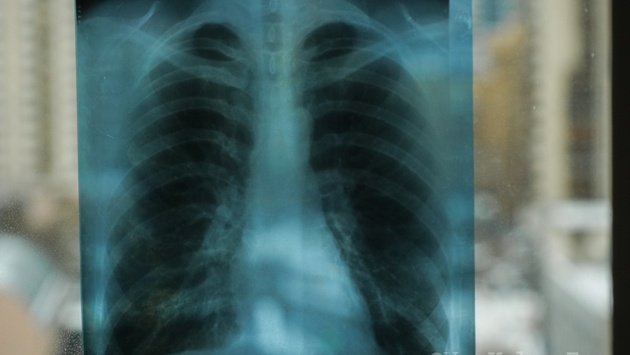

За год в Тюменской области больше 20 детей заразились туберкулезом

В Тюменской области за 2024 год не менее, чем у 567 человек обнаружили туберкулез. Среди них носителями инфекции стали 22 ребенка, следует из данных регионального управления Роспотребнадзора.

"Не меньше 22 детей заразились туберкулезом. По данным областного Роспотребнадзора, за прошлый, 2024 год всего инфекцию выявили не меньше, чем у 567 жителей нашего региона", – приводит данные ведомства портал 72.RU.

Уточняется, что Роспотребнадзор отказался называть точное число заболевших. Однако в ведомстве заявили, что количество заразившихся стало на 10% меньше в сравнении с 2023 годом, когда инфекция была выявлена у 630 жителей региона.

Основная доля носителей инфекции приходится на Тюмень и Тюменский район. Чаще всего причиной заболевания является контакт с зараженными, подчеркивают санитарные врачи.